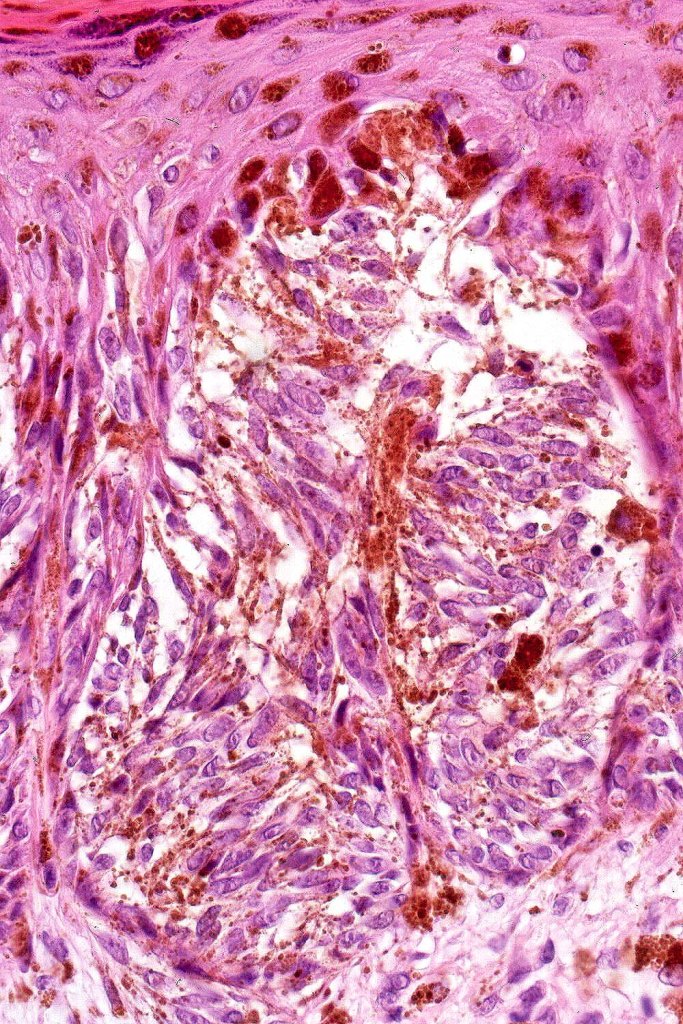

•Vertically orientated oval junctional nests

. Heavy pigmentation although hypopigmented/amelanotic varinats can be encountered

•Spindle cells with small nucleoli

•Mild pleomorphism

•Kamino bodies